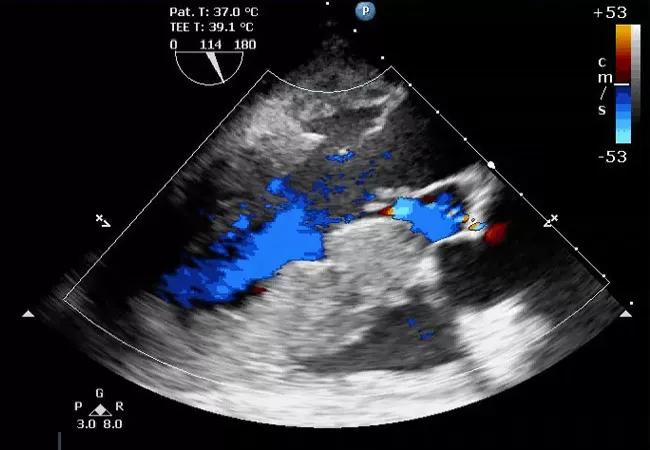

He was given epinephrine, and a norepinephrine infusion was started at 20 micrograms per minute. A transesophageal echocardiography (TEE) probe was placed and revealed a large pericardial effusion (Figure 1).

Figure 1. TEE findings showing a large pericardial effusion.